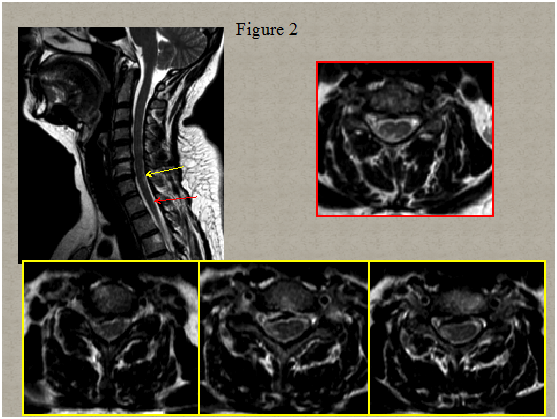

Immediate magnetic resonance imaging (MRI) of the spine was performed that showed degenerative changes with a herniated disc present at C5-C6 and C6-C7 level pressuring the spinal sac and cord and a centrolateral right disc hernia without pressure on the cord Figure 1. Two days after clinical onset electrical stimulation of the median, ulnar and peroneal nerves showed normal excitability of the right hand and leg muscles. Somato sensory evoked potentials of upper and lower limbs were normal. A second spinal MRI scan 5 days later revealed multiple abnormal T2 signals in the right lateral spinal cord from C6 to C7 and in the posterolateral spinal cord in T1/T2 Figure 2. Computed tomography angiogram of the chest, abdomen, and pelvis showed no dissection of the aorta. Tran esophageal echocardiography to evaluate for cardiac embolic source was normal. Cervical ultra sonogram showed no arteriosclerotic lesions.

Figure 2 Spinal cord MRI scan 5 days later demonstrated multiple abnormal T2 signals in the right lateral spinal cord from C6 to C7 and in the poster lateral spinal cord in T1/T2. T2 weighted sagittal image (a), axial image (b) corresponding to T1/T2 level and (c,d,e) corresponding to the lower cervical level.